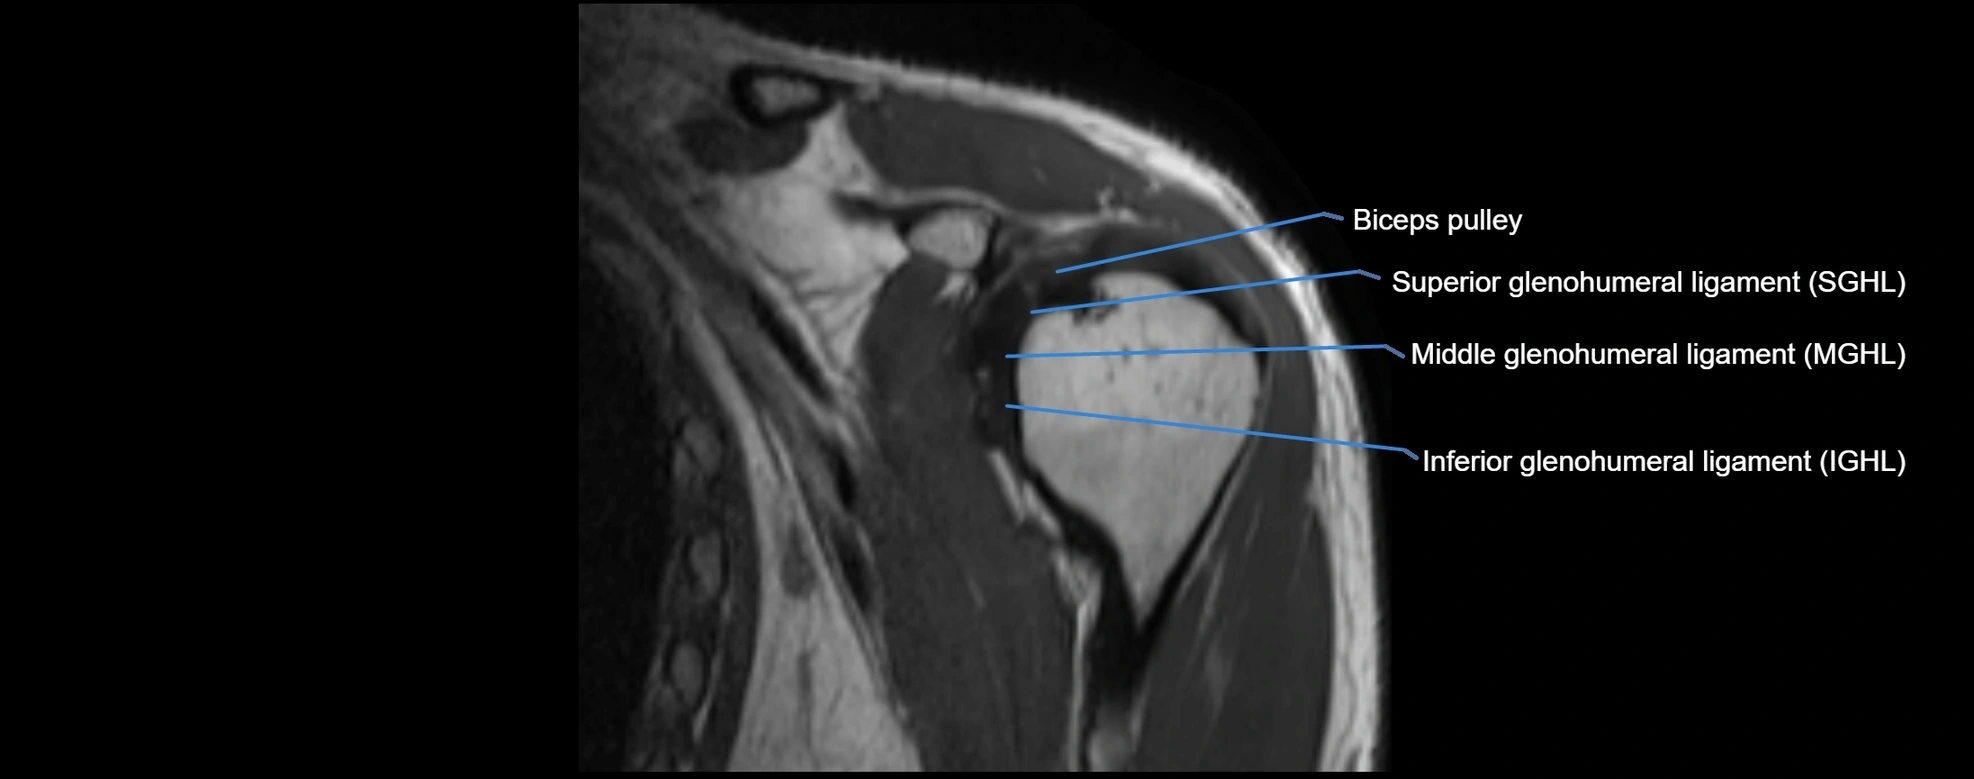

MRI Appearance

• T1-weighted images:

• Normal ligament: Low signal (dark linear band) spanning acromion to clavicle.

• Surrounding fat planes: Bright, delineating the ligament clearly.

• Marrow of clavicle and acromion: Bright due to fatty content.

• Tears: Discontinuity or irregular thickening with intermediate-to-bright signal.

• Chronic injury: Thinning, fraying, or irregular low-signal fibers with adjacent scarring.

• T2-weighted images:

• Normal ligament: Low signal, homogeneous.

• Partial tear or sprain: Focal hyperintensity or thickening.

• Complete tear: Discontinuity with fluid-bright gap between clavicle and acromion.

• Associated edema: Bright signal in distal clavicle or acromion marrow.

MRI images

image